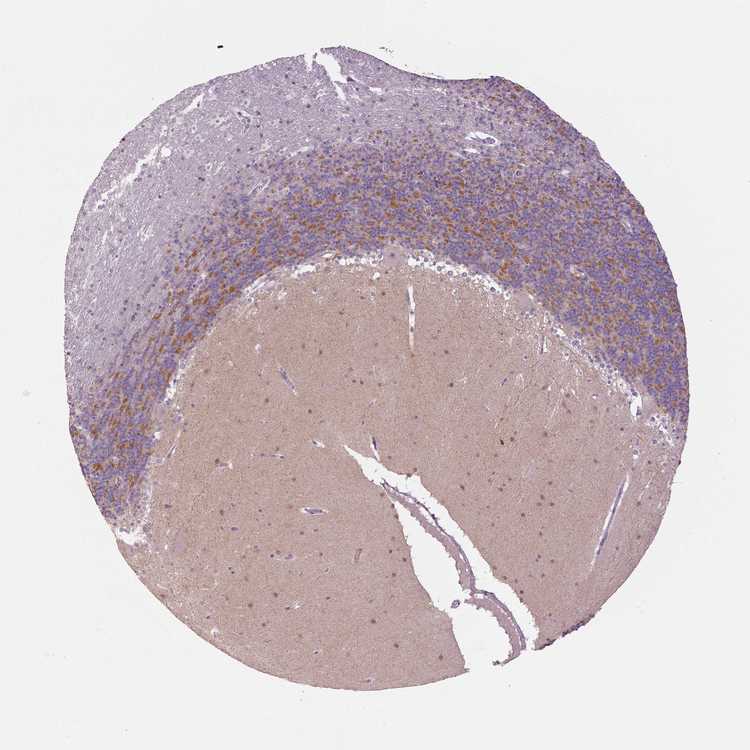

BRAIN CEREBELLUM Show tissue menu

CEREBELLUM - Expression summary

CEREBELLUM - Antibody stainingi

Antibody staining in the annotated cell types in the current human tissue is reported as not detected, low, medium, or high, based on conventional immunohistochemistry profiling in selected tissues. This score is based on the combination of the staining intensity and fraction of stained cells.

Each image is clickable and will lead to virtual microscopy that enables deeper exploration of all samples and also displays staining intensity scores, fraction scores and subcellular localization as well as patient and tissue information for each sample.

Antibody HPA069278

Bergmann glia - cytoplasm/membrane Not detected

Bergmann glia - nucleus Not detected

GLUC cells - cytoplasm/membrane Not detected

GLUC cells - nucleus Not detected

Purkinje cells - cytoplasm/membrane Not detected

Purkinje cells - dendrites Not detected

Purkinje cells - nucleus Not detected

Granular cells - cytoplasm/membrane Not detected

Granular cells - nucleus Not detected

Molecular layer - neuropil Low

Molecular layer cells - cytoplasm/membrane Medium

Molecular layer cells - nucleus Medium

Processes in granular layer Not detected

Processes in molecular layer Not detected

Processes in white matter Not detected

Synaptic glomeruli - capsule Not detected

Synaptic glomeruli - core Medium

White matter cells - cytoplasm/membrane Not detected

White matter cells - nucleus Medium